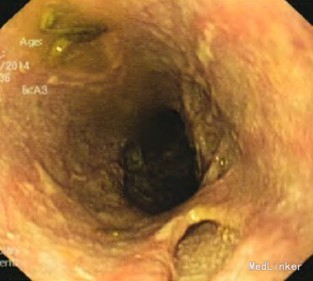

入院后查体:神志清楚,消瘦貌,中度营养不良。双肺听诊呼吸音粗,未闻及干湿性啰音。心律齐,各瓣膜听诊区未闻及病理性杂音。腹平,无腹壁静脉曲张,未见肠型、蠕动波。腹软,剑突下轻压痛,无反跳痛,无肌卫,移动性浊音阴性,肠鸣音约4次/min。 入院后行胃镜检查示食管中下段散在数条沿食管纵轴向下延伸的条索状裂陷或口疮样溃疡灶,部分深潜呈窦道样改变(见图1~2)。 病理报告单:(食道)鳞形上皮黏膜急慢性炎,见部分坏死、肉芽组织,H.pylori(-)。 肠镜及全消化道造影检查未见明显器质性疾病。 全胸片示:右侧胸腔积液,右上肺斑片状及纤维索条状状影。

入院后初步诊断为食管结核,予以抗痨治疗后效果欠佳,后经全院病例讨论考虑食管Crohn病的可能性较大,加用强的松40mg qd,美莎拉嗪0.75g bid治疗一周后,临床症状明显缓解,故诊断为:1.食管Crohn病,2.两肺陈旧性结核。